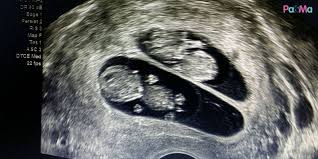

Secara umum, kehamilan kembar terjadi pada 1 dari 250 kehamilan. Ada yang kata, jika kita teratur minum susu dari zaman. Anak kembar sendiri dapat terjadi lantaran adanya dua sel sperma yang membuahi dua sel telur secara bersamaan. Kebanyakkan wanita mengandung selalunya teringin untuk mempunyai anak kembar kerana anak kembar kelihatan sangat comel dan semestinya membesarkan mereka akan mengukir sebuah pengalaman yang sangat. Perlu dilakukan cara khusus untuk dapat meningkatkan kemungkinan sepasang suami istri mendapatkan anak kembar. Ini kerana ubat tersebut dapat meningkatkan tahap kesuburan dengan merangsang pengeluaran sperma atau telur. Namun, ada beberapa cara yang bisa meningkatkan peluang anda untuk mendapatkan kami punya fitur baru untuk anda, ayo gunakan dan dapatkan manfaatnya untuk kesehatan anda. Namun, untuk pelaksanaanya tidak dapat dilaksanakan dengan sendiri.

Macam mana nak dapatkan anak kembar? Namun, jika anda merasa berat dengan cara di atas, anda dapat berkonsultasi langsung seputar masalah keturunan dengan kang masrukhan. Bagi sejumlah orang memiliki anak kembar adalah hal yang paling didambakan. Mengandung bayi kembar dapat terjadi pada satu buah sel telur wanita yang telah dibuahi, maka memiliki anak kembar adalah sebuah keinginan terbesar dari beberapa pasangan orangtua. Kehamilan bayi kembar bisa saja terjadi jika beberapa faktor pendukungnya terpenuhi.